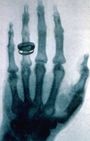

- 1895 - أثناء اجرائه تجارب على الكهرباء، العالم والطبيب الألماني "ڤيلهلم رونتگن" يكتشف الأشعة السينية المعروفة بأشعة إكس. نال ڤيلهلم رونتجن جائزة نوبل في الفيزياء عام 1902 مكافأة على هذا الاكتشاف.